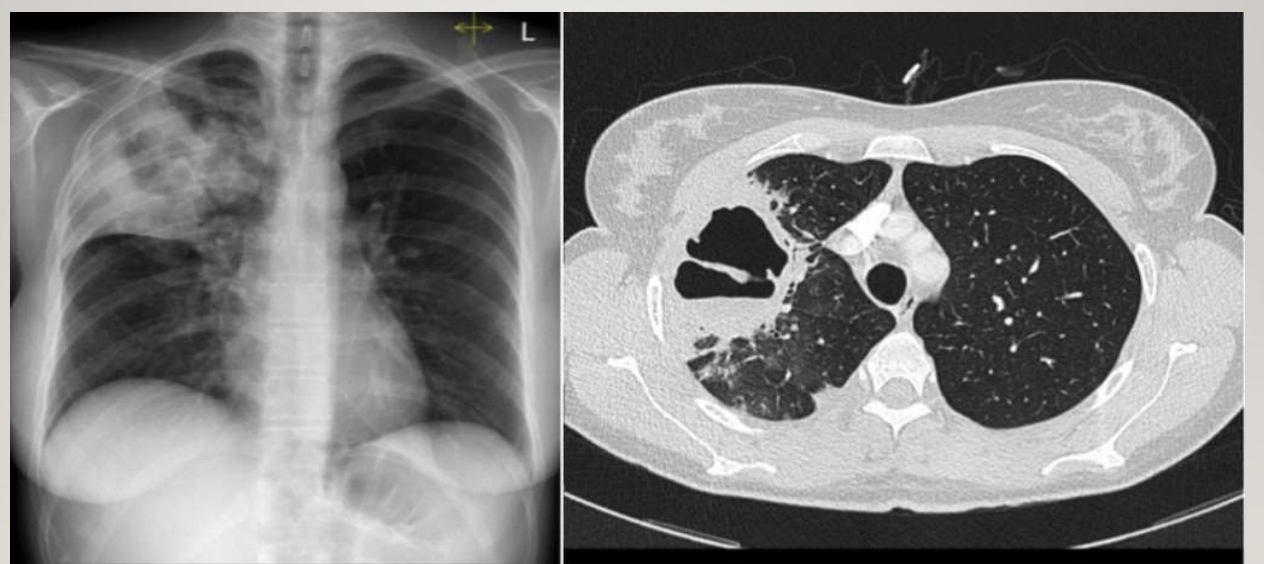

Not at all

2

4

5